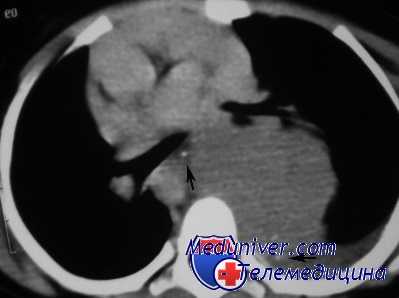

КТ ОГК. Массивное объемное образование верхнего средостения с объемным воздействием на трахею, исходящее из щитовидной железы.